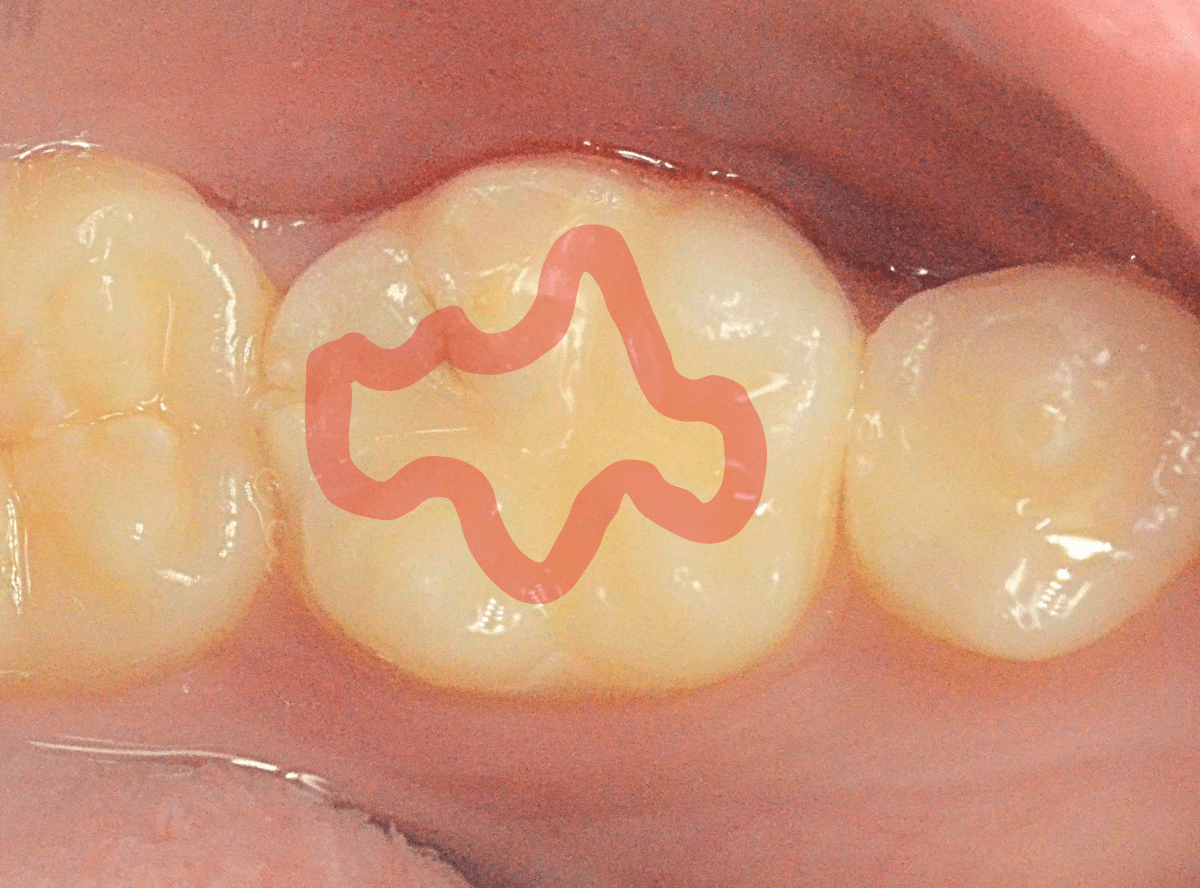

Case.25 深い虫歯の治療~無事にセラミック・インレーへ

今回は、上の奥歯が深くて広い虫歯になっていた方のケースです。

〇部が虫歯の部分です。

この写真からは深い虫歯があるのは想像つきません。

レントゲン写真で確認します。

青い線が神経、赤い線が虫歯の部分です。

前後の歯とも、かなり深く広い虫歯になっているのがわかります。